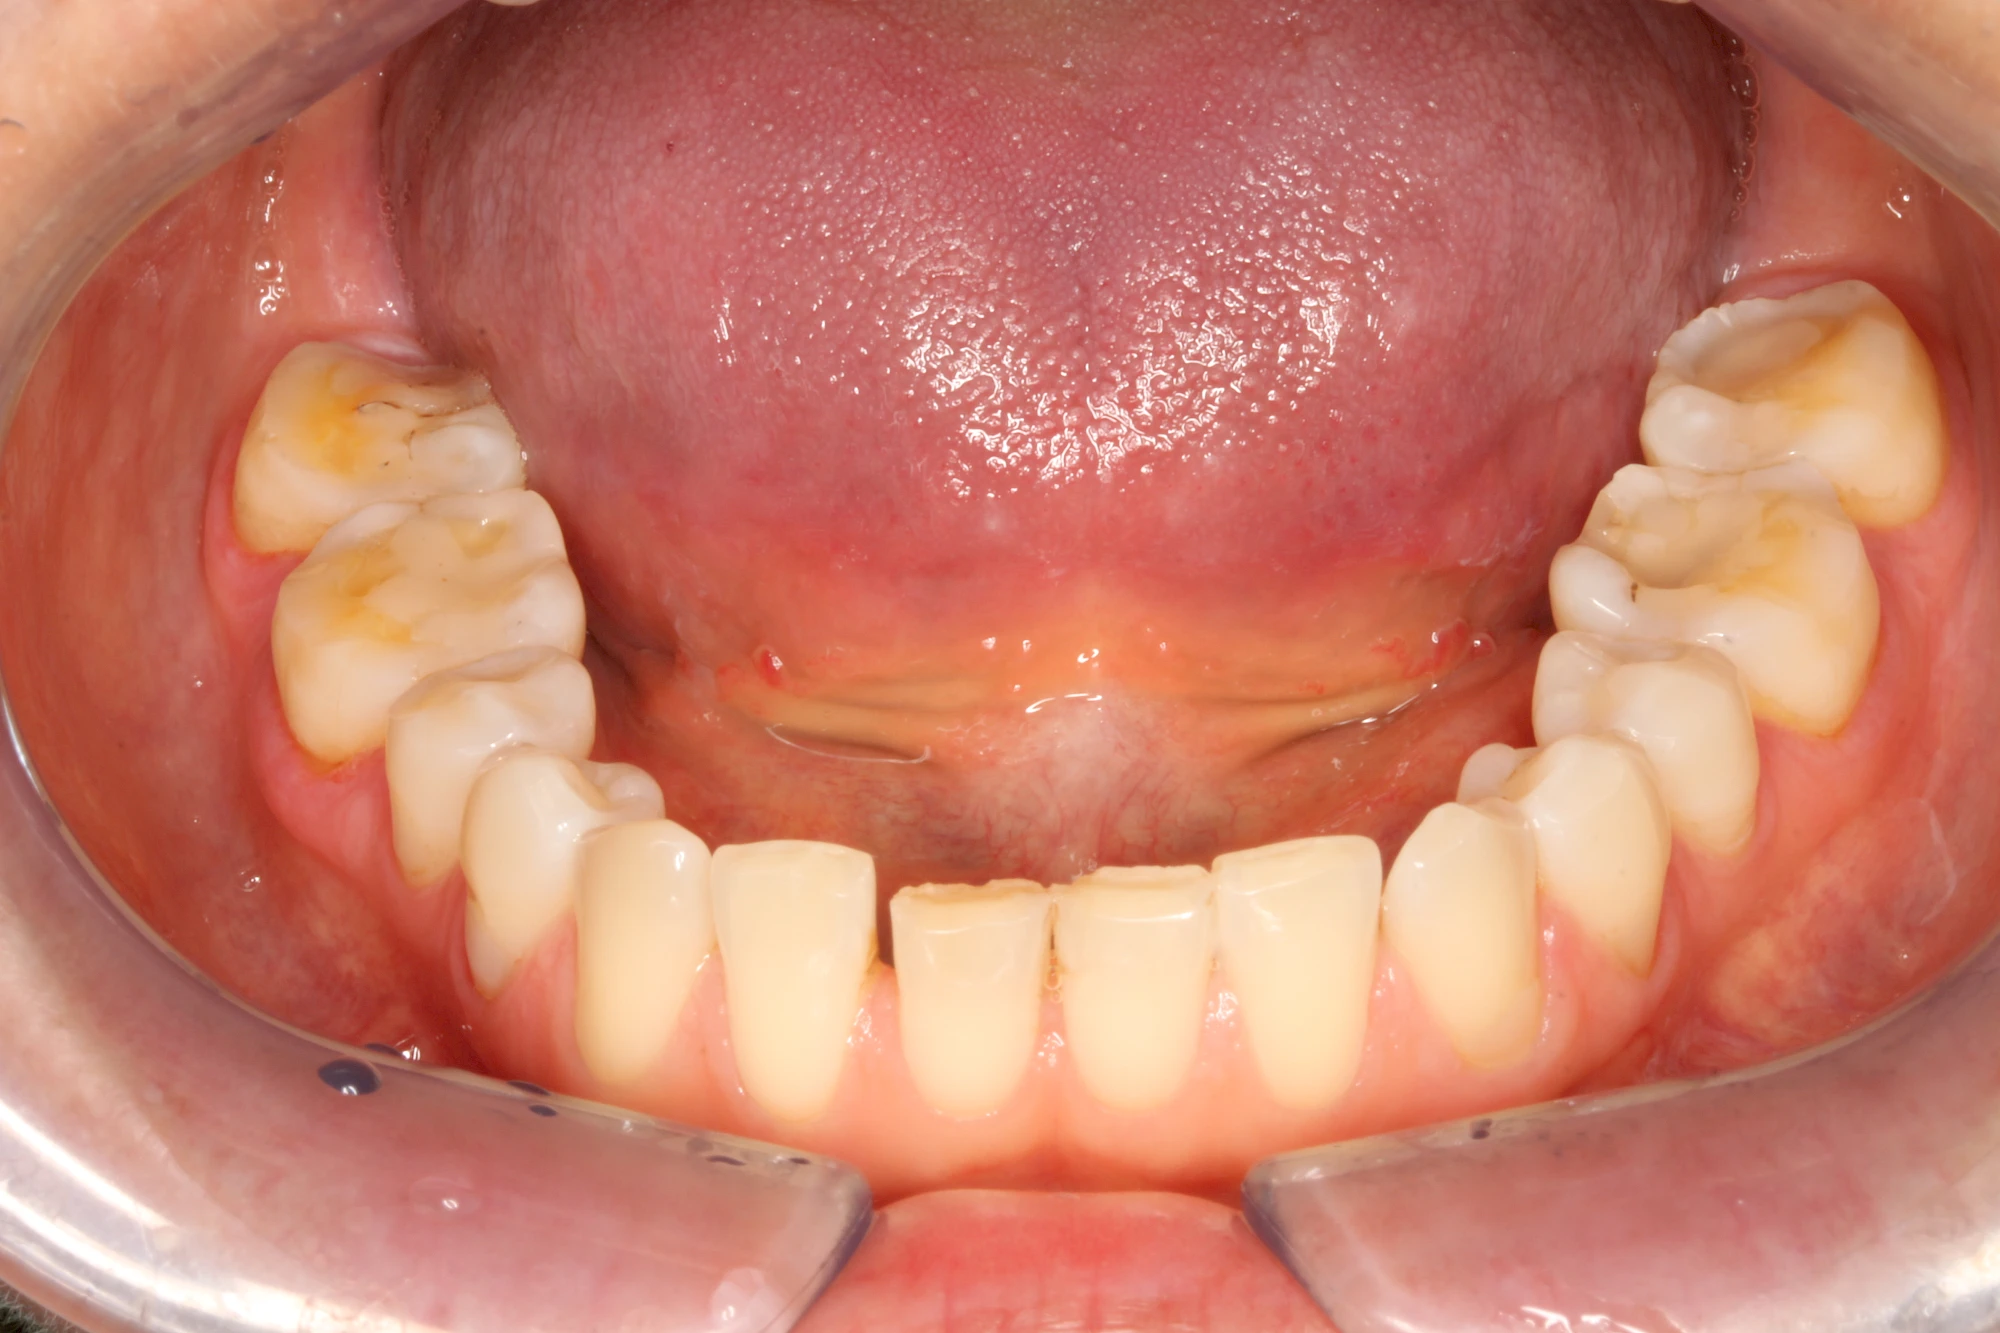

Keilförmiger Defekt

Eine Sonderform sind sogenannte keilförmige Defekte im Bereich der Zahnhälse. Hier geht man davon aus, dass Knirschen und Pressen in Kombination mit falschen Putzgewohnheiten (zu hoher Putzdruck, Verwendung von Zahnpasta mit hohen Abrasionswerten) eine Rolle spielen.